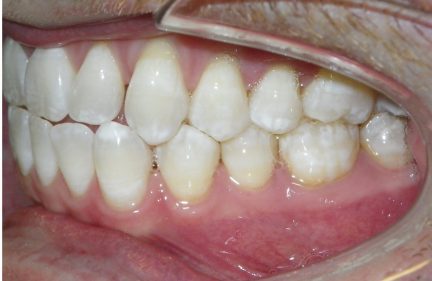

État initial

- La béance antérieure de classe III a été corrigée par une combinaison d'égression active absolue des dents antérieures supérieures ainsi que d'une inclinaison des incisives

- La rétraction des dents antérieures inférieures en utilisant l'espace existant ainsi que l'espace gagné en effectuant une réduction interproximale et avec l'usure élastique de classe III ont contribué à la correction de la béance antérieure